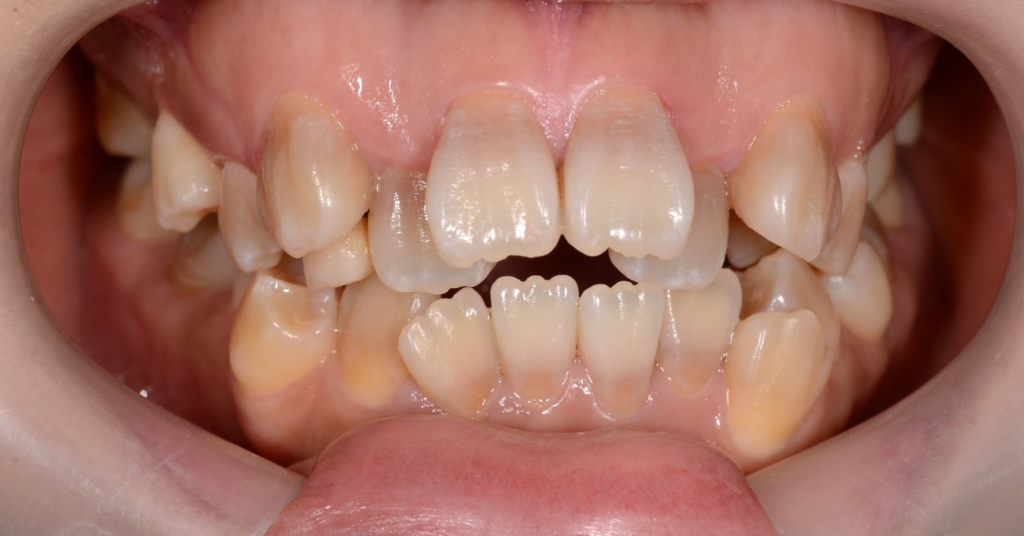

患者さんは、20代の女性(社会人)です。

「八重歯などのガタガタを治してきれいな歯並びになりたい!」

#1.顎と歯の不調和による叢生(重度)

#2.上顎前突(出っ歯)

#3.開口

と診断しました。